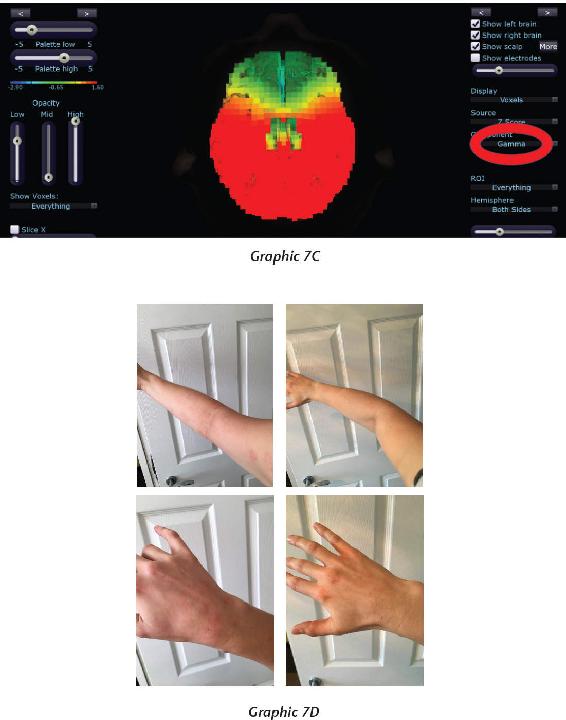

At the end of 2013, something mysterious started occurring. We started seeing brain scan recordings that puzzled the researchers and neuroscientists who came to our events to study my work. The high amount of energy in the brain that we were recording while a student was in certain meditations had never been recorded up until this point. And yet we were seeing these off-the-charts readings again and again.

When we interviewed the participants, they reported that their subjective experience during the meditation was very real and mystical, and that this either profoundly changed their view of the world or dramatically improved their health. I knew in those moments that these participants were having transcendental experiences in their inner world of meditation that were more real than anything they had ever experienced in their outer world. And we were capturing those subjective experiences objectively.

That has become a new normal for us now, and as a matter of fact, we can often predict when these high amplitudes of energy in the brain will occur, based on certain indicators and signs that we have seen for years now. In these pages, I want to demystify what it is to have an interdimensional experience as well as provide the science, biology, and chemistry of the organs, systems, and neurotransmitters that make this happen. It is my hope that this information will give you a road map for how to create such experiences for yourself.

Other centers in your body besides the heart are also under the control of the autonomic nervous system—I call them energy centers. Each has its own frequency, its own intent or consciousness, its own glands, its own hormones, its own chemistry, its own individual little brain, and so its own unique mind. You can influence these centers to function in a more balanced and integrated fashion. But to do that, you must first learn how to change your brain waves so you can enter this subconscious operating system. In fact, moving from beta brain waves (where the thinking brain is constantly analyzing and putting much attention on the outer world) to alpha brain waves (which indicate you’re calmly placing more attention on the inner world) is key. By consciously slowing your brain waves down, you can more readily program the autonomic nervous system. Students who’ve done my various meditation practices over the years have learned how to change their brain waves as well as sharpen the type of focus it takes to be present long enough to produce measurable effects. We’ve discovered an instrument that can measure those changes, and again, I’ll show you some of the research.